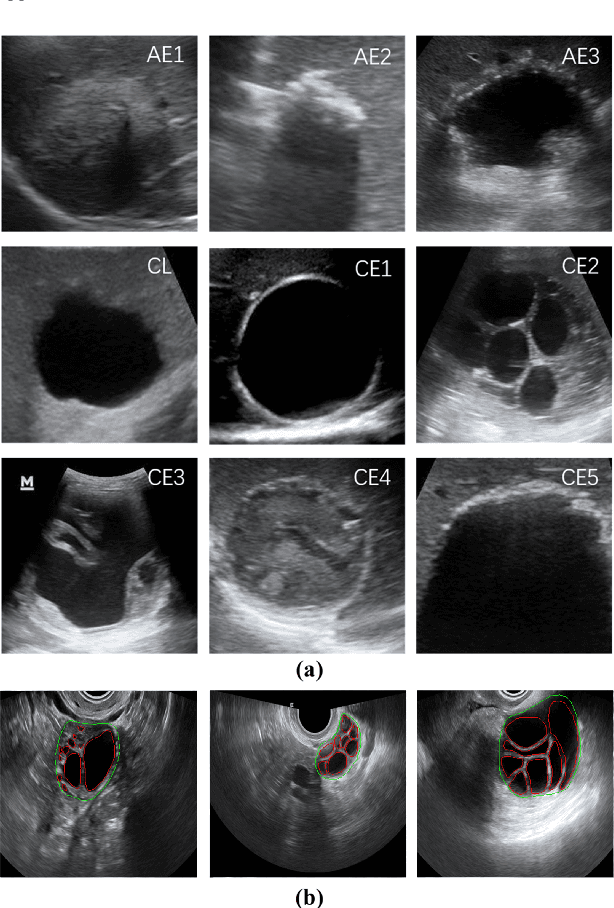

Different from handcrafted features, deep neural networks can automatically learn task-specific features from data. Due to this data-driven nature, they have achieved remarkable success in various areas. However, manual design and selection of suitable network architectures are time-consuming and require substantial effort of human experts. To address this problem, researchers have proposed neural architecture search (NAS) algorithms which can automatically generate network architectures but suffer from heavy computational cost and instability if searching from scratch. In this paper, we propose a hybrid NAS framework for ultrasound (US) image classification and segmentation. The hybrid framework consists of a pre-trained backbone and several searched cells (i.e., network building blocks), which takes advantage of the strengths of both NAS and the expert knowledge from existing convolutional neural networks. Specifically, two effective and lightweight operations, a mixed depth-wise convolution operator and a squeeze-and-excitation block, are introduced into the candidate operations to enhance the variety and capacity of the searched cells. These two operations not only decrease model parameters but also boost network performance. Moreover, we propose a re-aggregation strategy for the searched cells, aiming to further improve the performance for different vision tasks. We tested our method on two large US image datasets, including a 9-class echinococcosis dataset containing 9566 images for classification and an ovary dataset containing 3204 images for segmentation. Ablation experiments and comparison with other handcrafted or automatically searched architectures demonstrate that our method can generate more powerful and lightweight models for the above US image classification and segmentation tasks.